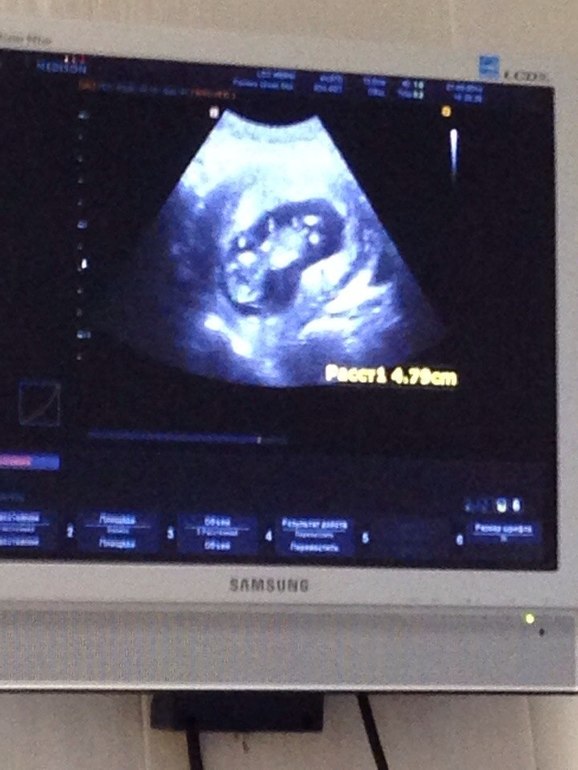

УЗИ в 13,3 нед

По результатам УЗИ все хорошо, только уже второе УЗИ показывает тонус, но я не чувствую его постоянно, иногда ощущаю дискомфорт внизу живота, но нечасто. Гиня, кстати, несколько раз меня осматривала после первого УЗИ, говорит не чувствует тонуса. Ну и срок по М на 2 недели опережает срок по УЗИ. По УЗИ малышка сейчас соответствует 11,5 нед. А в 9 нед по М УЗИ показывало 7 нед. Уже второй врач ссылается на позднюю овуляцию. Г пока ничего не говорит по этому поводу, но и меня пока это не особо волновало. Завтра на прием, поговорим с ней об этом.

КТР 48 мм

ЧСС 174 уд/мин

ПДР 24 сентября

Фото на память распечатали и несколько снимков с монитора сделали

Делали УЗИ в хорошей платной клинике, разрешили присутствовать мужу с ребенком. Нам не с кем его оставлять, поэтому Тёма всегда с нами)) Муж с умилением наблюдал за процессом. Дала ему телефон, попросила пофоткать ляльку на мониторе, потом вышли, смотрю, а у меня 3 фото в телефоне. Муж даже от эмоций забыл о моей просьбе)) Ну и Тёма можно сказать уже познакомился с... СЕСТРИЧКОЙ!) Похоже, нам везет с врачами! Врач долго высматривал пол, потом выдал: "Судя по этому хвостику на мониторе у вас девочка!" Конечно, я пока не очень доверяю, срок маленький, но вероятность 50/50. Может это и мальчика хвостик)))